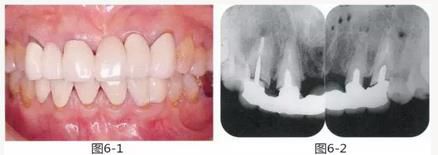

圖6-1

上頜前牙的牙頸部及齦下存在齲壞。

圖6-2 初診時的X光照片。齦下齲壞延伸到牙槽嵴頂,根管治療也不徹底。